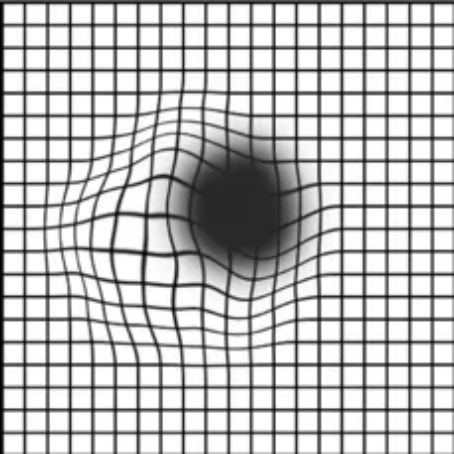

对于高风险人群,可以通过阿姆斯勒方格表观察视物是否变形:

看图测“黄斑病变”:

1. 如有老花或近视,需配戴原有的眼镜进行测试;

2. 把方格表放在视平线30厘米处,光线要清晰且平均;

3. 用手掌盖住左眼,右眼凝视方格表的中心黑点;

4. 重复以上步骤,检查左眼。

↑ 以上表格

你看到的是以下哪张图的样子?↓

图1

图2

图3

查看答案

图1:恭喜你,眼底黄斑正常!

图2或图3:眼底黄斑出现了问题!